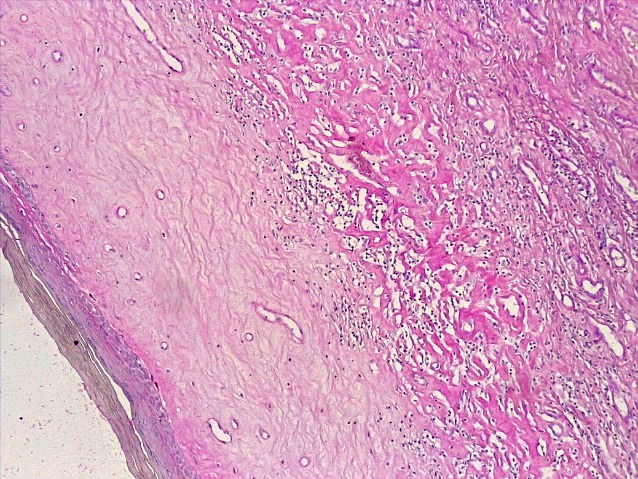

При проведении морфологического исследования тканей вульвы пациенток со склероатрофическим вариантом течения СЛВ также отмечалась резкая атрофия кожи за счет клеток эпидермиса и дермы, уменьшение клеточных слоев эпидермиса от 2–3 до 4–5 с участками повышенного ороговения (гипрекератоз). Количество базального слоя было снижено в разных случаях от 2–3 до 5–6 клеток в 1 мкм, что указывало на снижение функционального резерва эпидермиса. В случае длительного течения заболевания клетки базального слоя имели признаки дистрофии. В поверхностных слоях дермы отмечался фиброз с отложением масс гиалина, а также редукция кровеносных сосудов мелкого калибра, окруженных клеточным воспалительным инфильтратом из лимфоцитов и макрофагов (рис. 14–17).

Рис.16. Склероатрофический вариант течения СЛ. Неравномерная атрофия и гиперкератоз многослойного плоского эпителия, умеренновыраженное хроническое воспаление дермы с развитием фиброзной ткани (окраска гематоксилином-эозином, х100)

Fig.16. Scleroatrophic variant of the course of SL. Uneven atrophy and hyperkeratosis of the multilayer squamous epithelium, moderate chronic inflammation of the dermis with the development of fibrous tissue ((hematoxylin-eosin staining, x 100)

Рис. 17. Склероатрофический вариант течения СЛ. Резкая атрофия клеток эпидермиса, слабовыраженная лимфо-гистиоцитарная инфильтрация поверхностных слоев дермы, фиброзная ткань в дерме (окраска гематоксилином-эозином, х100)

Fig.17. Scleroatrophic variant of the course of SL. Sharp atrophy of epidermal cells, weakly expressed lymphohistiocytic infiltration of the surface layers of the dermis, fibrous tissue in the dermis (hematoxylin-eosin staining, x 100)